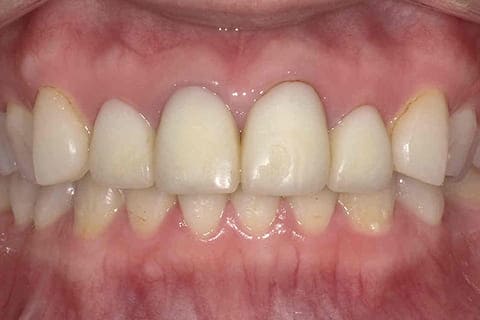

健康に美しく臨床実績集

虫歯や歯周病、事故などでの欠損、

噛めるようになりたい、見た目の美しさの追求など、

審美的に機能的に回復した治療経過報告症例です。